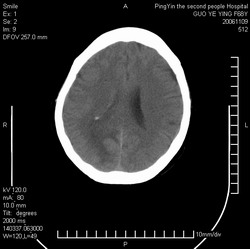

郭*,61岁 ,头痛半月并有复视

右侧颞枕叶见形态不规则等密度灶,灶周可见水肿灶,考虑:1、胶质瘤?2、转移瘤?建议做增强或mri检查

右侧颞枕叶见形态不规则等密度灶,中心见低密度影,灶周可见水肿明显,右侧脑室受压变窄,考虑胶质瘤或转移瘤。请作增强或mri检查

可见两个大小不等环形结节灶伴瘤周水肿.

意见:转移瘤.

平扫观察右侧至少有3个结节伴周围水肿,首先考虑转移。先查肺部吧。

右侧脑实质内多发结节影并指状水肿.

意见:考虑多发转移瘤.

右侧颞枕叶见多个形态不规则等密度灶,中心见低密度影,灶周可见水肿明显,右侧脑室受压变窄,考虑转移瘤或胶质瘤。请作增强或mri检查